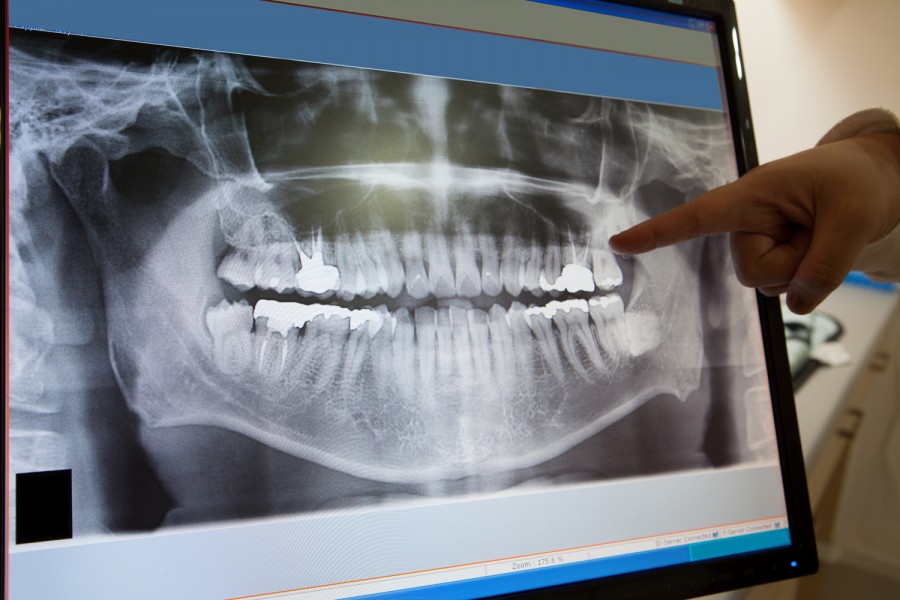

Mükemmel bir ağız ve diş sağlığını korumanın anahtarı, potansiyel sorunların erken tespit edilmesidir. Bu nedenle Sezer Diş’te en son dijital ve panaromik röntgen teknolojilerini kullanıyoruz, ayrıca dijital sistemin kullanılması görüntü kalitesini artırmakta ve hastaların maruz kaldığı radyasyon miktarını belirgin şekilde azaltmaktadır. Dijital röntgenlerimiz, çıplak gözle veya geleneksel röntgenlerle görülemeyen şeyleri görmemizi sağlar. Dijital röntgenler dişlerdeki çürük, kemik kaybı, kök kanalındaki ve diğer diş sağlığı sorunlarının erken tespitini sağlamanın en iyi yoludur. Aynı zamanda diş hekiminizin diş tedavisine başlamadan önce hızlı ve etkin bir şekilde planlama yapmasını sağlar.

Çoğu insan, röntgeni çürükleri bulmak için kullandığımızı düşünür. Oysa ki panaromik röntgen aynı zamanda kistleri, iyi huylu veya kanserli tümörleri, gömülü dişlerin yerini, çene ve kemik yapısının belirlememe yardımcı olabilir. İmplantlarınızı doğru yerleştirememiz  için panaromik röntgen paha biçilmezdir.

Dijital röntgenler, ağız ve diş sağlığı konusunda hastalara yardım etmek için kullandığımız çok yönlü ve en yararlı tanı yöntemlerinden biridir.